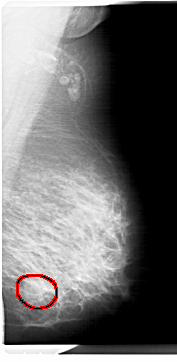

A_1298_1.LEFT_MLO

LEFT_MLO LINES 6871 PIXELS_PER_LINE 3481 BITS_PER_PIXEL 12 RESOLUTION 43.5 NON_OVERLAY

FILE: A_1298_1.RIGHT_MLO.OVERLAY

TOTAL_ABNORMALITIES 1

ABNORMALITY 1

LESION_TYPE MASS SHAPE ROUND MARGINS OBSCURED

ASSESSMENT 4

SUBTLETY 3

PATHOLOGY BENIGN

TOTAL_OUTLINES 1

BOUNDARY